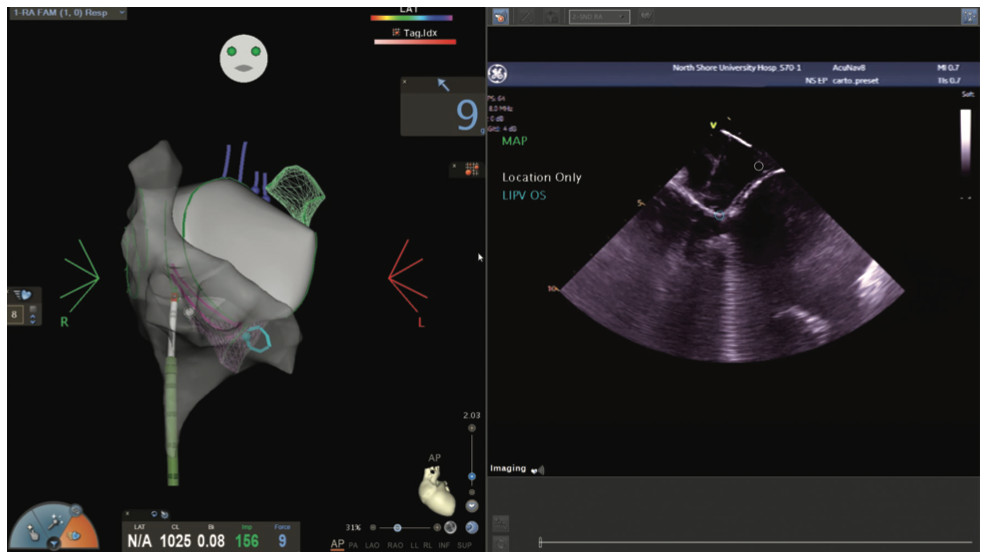

Figures/Videos 1-10 demonstrate the process of navigation from groin access to the heart to create biatrial geometry, localize the esophagus, and gain transseptal access. Many currently practicing electrophysiologists use very little fluoroscopy to map and ablate the left atrium (LA) with the current multielectrode catheters and EAM systems once transseptal access is obtained.